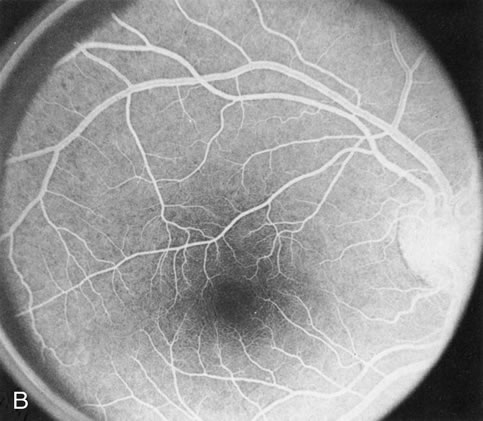

DOMINANT DRUSEN OF BRUCH'S MEMBRANE

There is no clear agreement as to what constitutes dominantly inherited drusen and what constitutes age-related degenerative drusen. There is a distinct group of younger individuals with bilateral, symmetric, uniformly small, round, discrete, yellow and white drusen. Histopathology demonstrates a nodular thickening of the RPE basement membrane, and these drusen have therefore been referred to as basal laminar, or cuticular, drusen.24

FA shows a characteristic pinpoint area of transmission hyperfluorescence corresponding to the drusen and reveals many more than are appreciated clinically (Fig. 12). Secondary changes such as pigment atrophy and dispersion, exudative and nonexudative detachments, and occasionally a neovascular membrane, will be revealed by FA (Fig. 12E).

Fig. 12. Dominant drusen of Bruch's membrane. The drusen appear as yellowish-white “blisters” predominantly in the temporal posterior pole (A). The angiogram shows many pinpoint areas of transmission hyperfluorescence typical of drusen, some of which have coalesced to form broader areas of hyperfluorescence (B). These drusen occasionally result in ingrowth of a choroidal neovascular membrane, such as occurred in this case over a 5-year period (C–E).